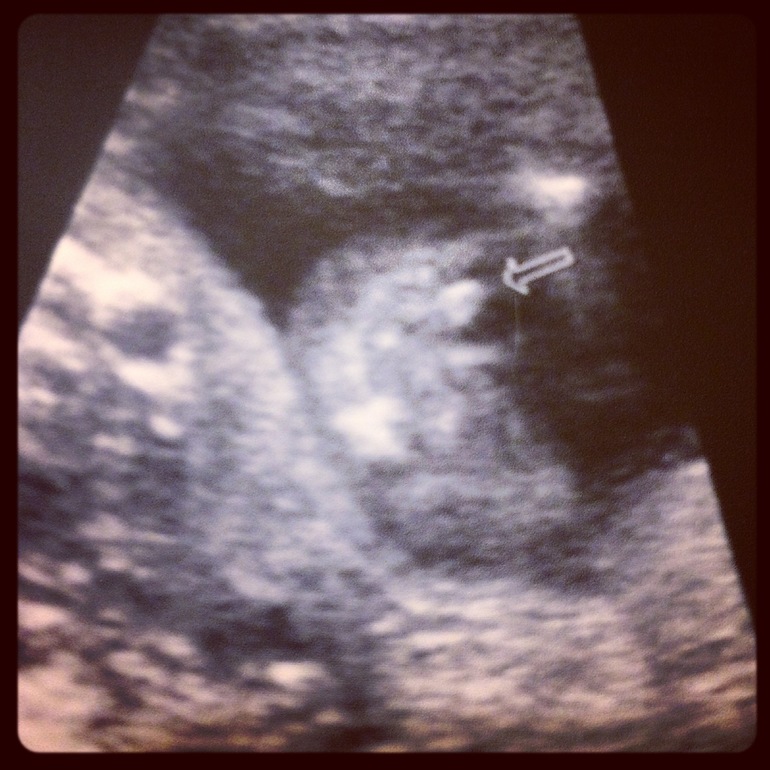

В общем, показывал и рассказывал он всё очень подробно, огромное ему спасибо. Показал мне личико, каждую косточку, ручки и ножки. Всё тщательно померил - всё у нас отлично и по сроку)) Вертел он меня, вертел (а я пока бежала растрясла малыша, он так брыкался!) и тут такой "Опа!" В общем, предположили нам мальчика, ибо для девочки "уж слишком торчит")) И так он его разглядывал, и эдак... Говорит "я не исключаю возможность ошибки, но очень сомневаюсь что там что-то изменится".

Фото, конечно, ужасного качества, но уж что есть. Вид снизу (со стороны попы)